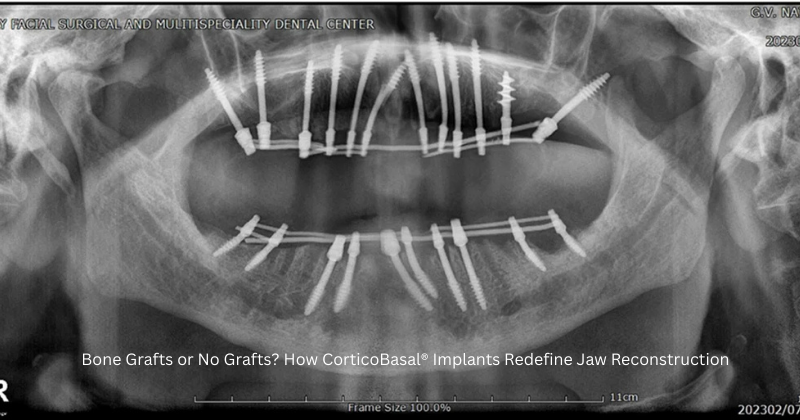

CorticoBasal® Implants utilize the dense cortical bone — a naturally strong layer of jawbone that does not resorb over time. This innovation, brought to clinical excellence by experts like Dr. Vivek Gaur, ensures immediate stability without waiting for grafts to heal.

- No bone grafting required:Even patients with significant bone loss qualify for treatment.

- Immediate loading:Teeth are fixed within 72 hours, 48 hours restoring full chewing function rapidly.

- Long-term durability:Cortical bone offers stable anchorage, minimizing failure risks.

This approach not only simplifies the process but also makes implantology more accessible for patients, who had insufficient bone strength and were rejected for traditional implants.